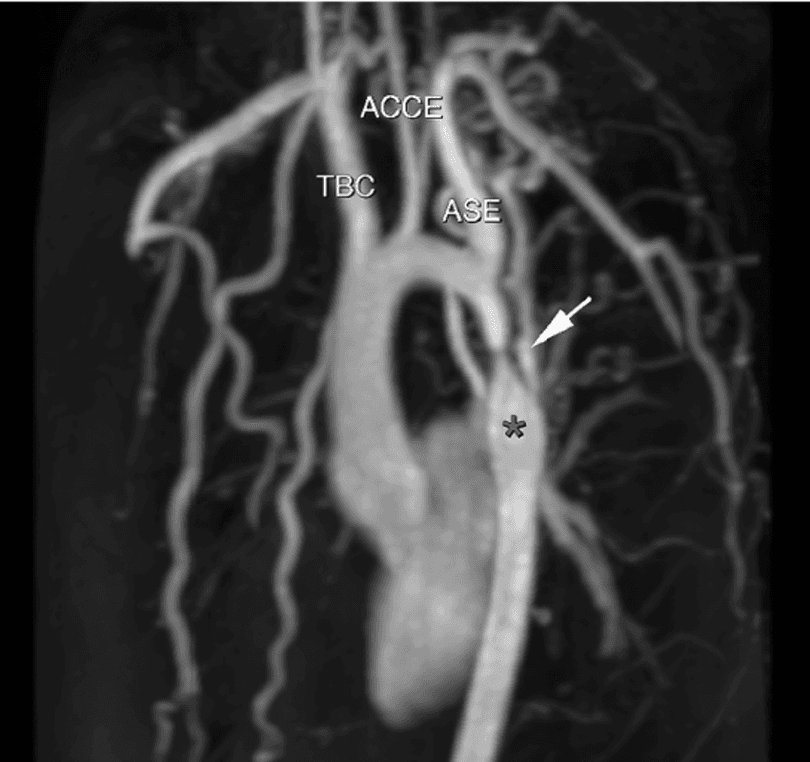

Consiste em estreitamento do lúmen da aorta situado na maioria das vezes ( 96% ) na região localizada entre a destino da artéria subclávia esquerda e a região do canal arterial ( istmo da aorta ).